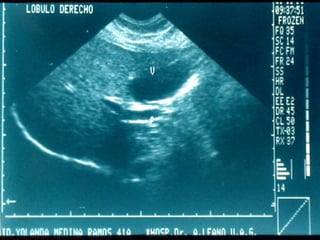

SONOGRAMA ABDOMINAL EVALUACIÓN HIGADO SISTEMA BILIAR BAZO  RIÑONES PANCREAS ( no específico)

SONOGRAMA ABDOMINAL EVALUACIÓNHIGADO SISTEMA BILIAR BAZO RIÑONES PANCREAS ( no específico)